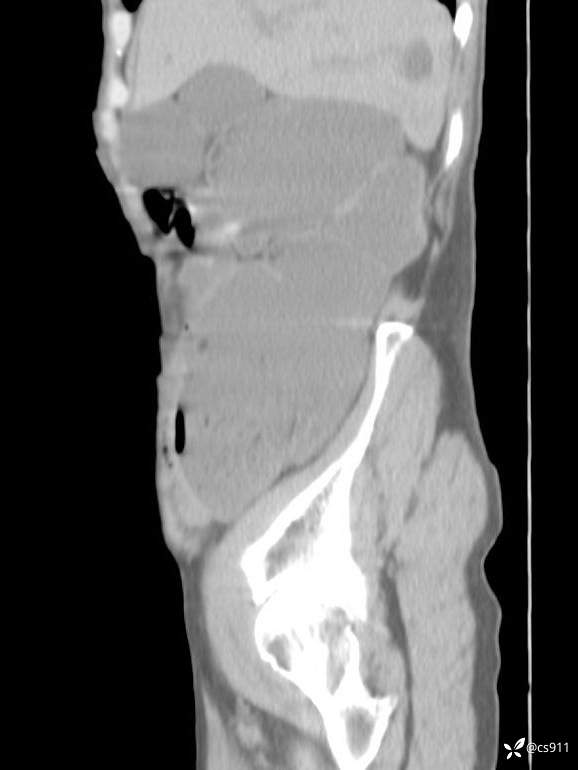

急腹症之急诊CT,原因?答案公布

男,77岁,腹痛、腹胀伴恶心呕吐1天。呕吐胃内容物,非喷射性呕吐,有咖啡色样胃内容物,诉有胃穿孔病史。查体:全腹平,下腹部压痛,全腹无反跳痛,叩诊呈浊音,移动性浊音阴性,肠鸣音减弱,1-2次/分。肛检:直肠未扪及明显肿物,可触及大量粪块。

T 36.6℃ P 80次/分 R 26次/分 BP 100/60mmHg

白细胞(WBC) H 14.55 10e9/L 4-10

红细胞(RBC) 4.58 10e12/L 4.3-5.8

中性粒细胞百分率(NEUT%) H 85.7 % 40-75

血淀粉酶(AMY) HH 1859 U/L 35-135

癌胚抗原(CEA) H 27.44 ng/ml 0-5

呕吐物 潜血试验 * 阳性 阴性

患者轮椅入室检查神志清楚, 能配合摆位和呼吸